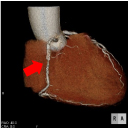

■3DCT検査

血管、臓器、骨の位置関係、状態を立体的(3D)に画像化し、手術支援等のために施行します。

腹部大動脈CTA(大動脈瘤)

整形外科3D(骨折)

脳血管3DCTA(脳動脈瘤)

冠動脈3DCTA(狭心症)